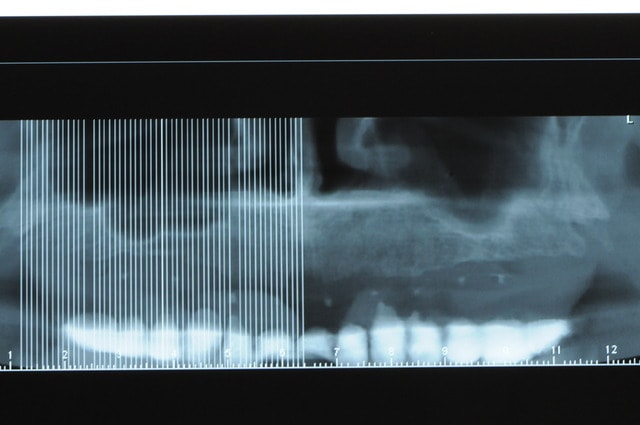

voili, voila...

avant de faire la tomosynthèse je comprenais pas pourquoi j'avais aussi peu de contraste.

le patient ne souhaite pas, ou ne peut pas se faire poser 6 implants en haut, donc...overdenture sur 4. (si possible)

4 mini implants de prévues en bas...